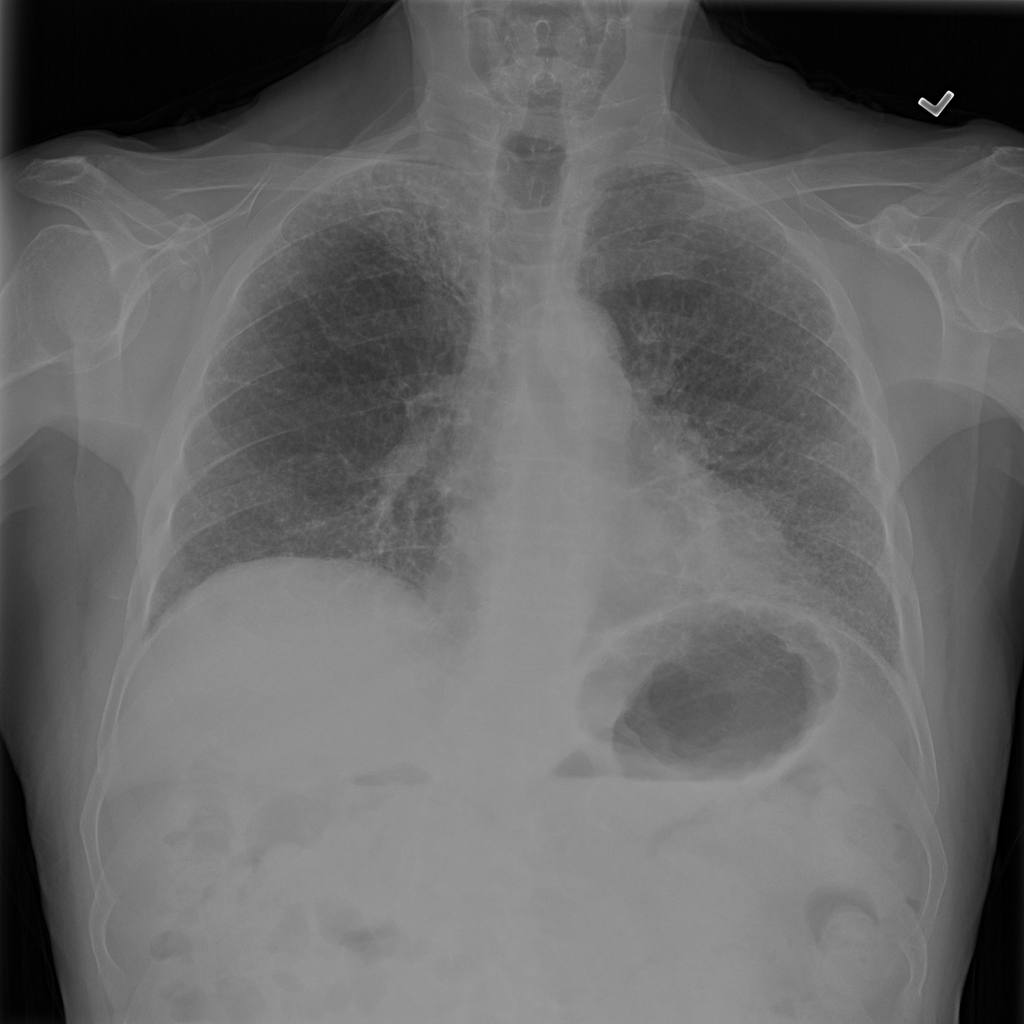

PAT-1F50 · IMG-000Fibrosis

PAT-1F50 · IMG-000

PA